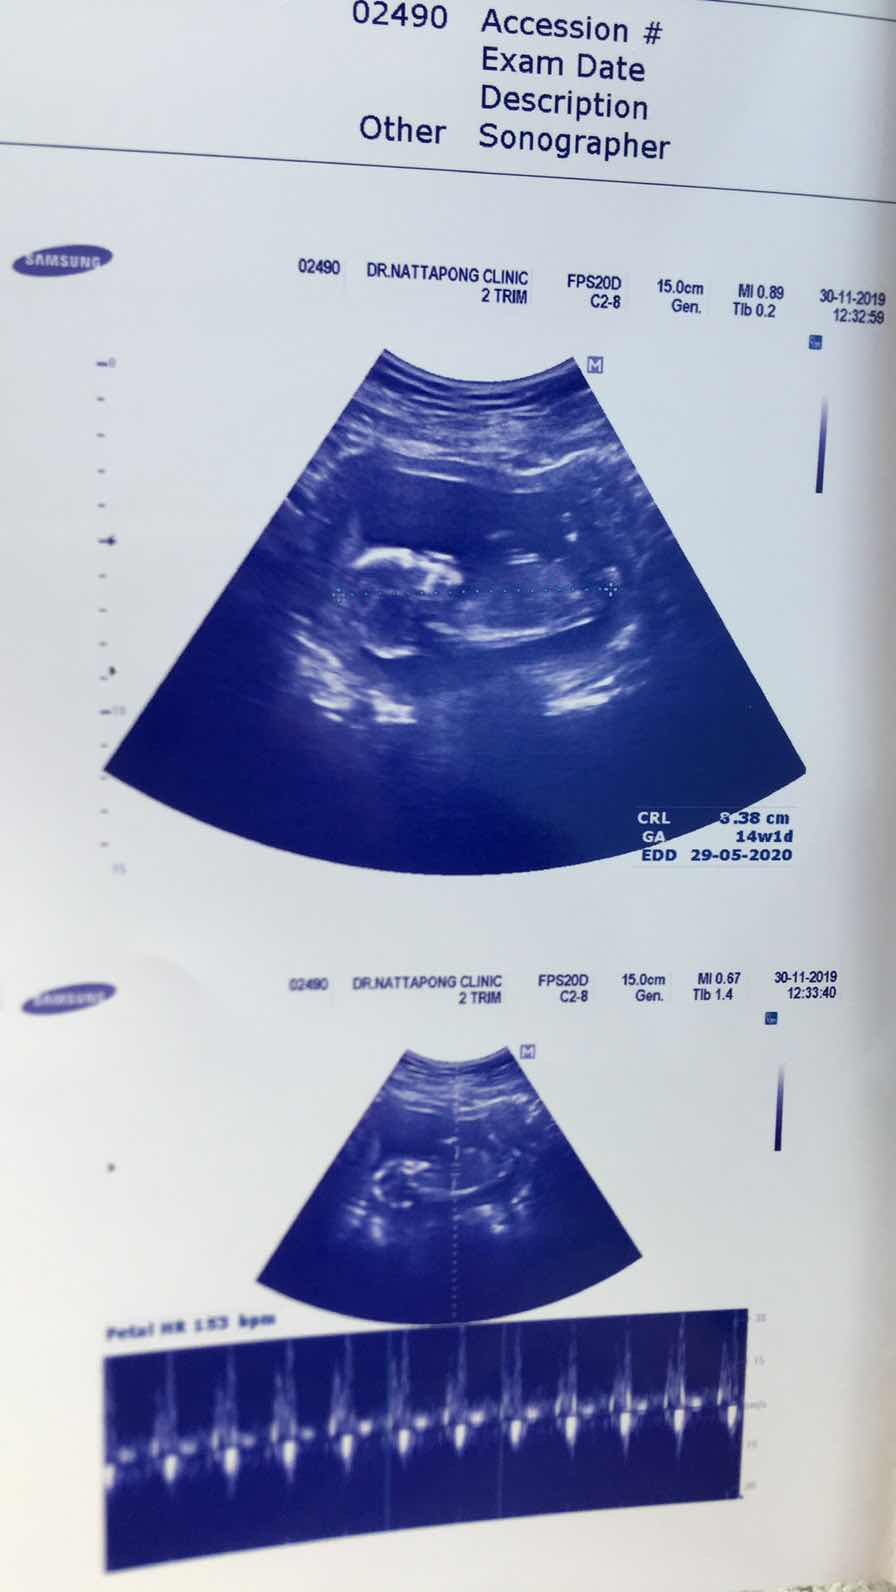

14วีค ค่ะก็เห็นประมาณนี้